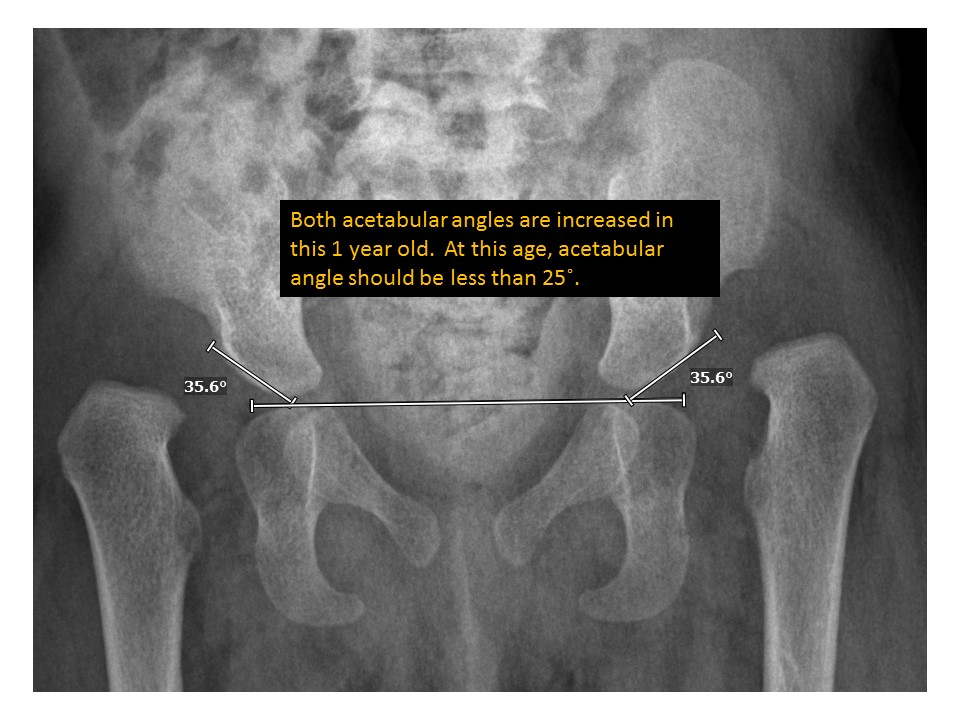

Findings